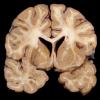

HIV Encephalitis (2)